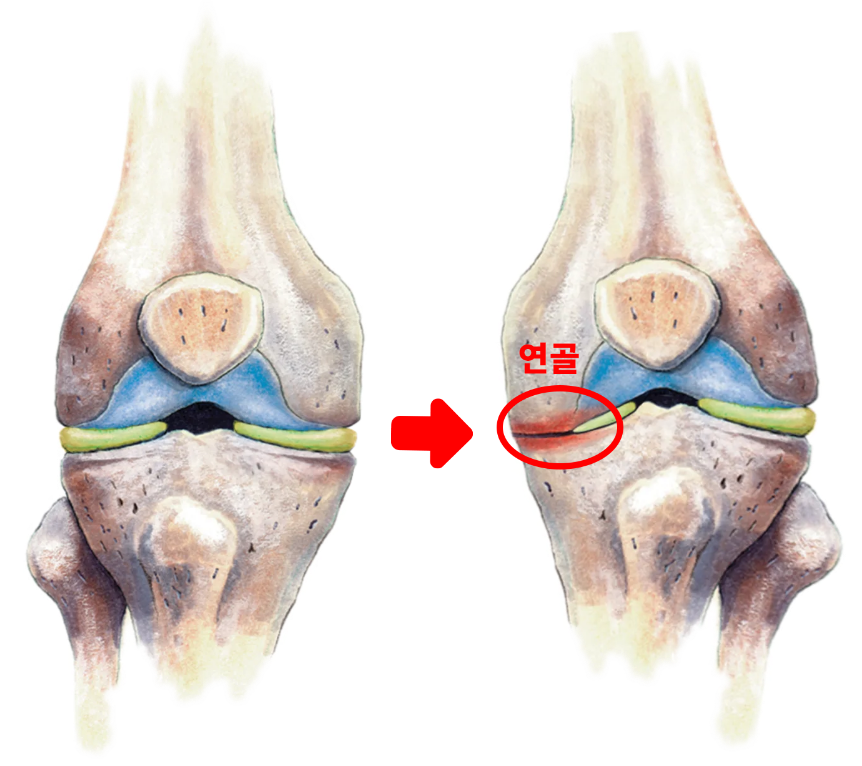

¹«¸ ÅëÁõ ¶Ç´Â °í°üÀý ÅëÁõ°ú °°Àº ¿¬°ñ ÅëÁõÀÇ °¡Àå ÈçÇÑ ¿øÀÎ Áß Çϳª´Â °üÀý ¿¬°ñÀÇ Á¡ÁøÀûÀÎ ÆÄ±«¸¦ ÀÏÀ¸Å°´Â ÁúȯÀÎ °ñ°üÀý¿°(osteoarthritis, OA)ÀÔ´Ï´Ù. °ñ°üÀý¿°Àº ¿¬°ñ ¼Õ»óÀ» À¯¹ß½ÃŰ´Â ÅðÇ༺ ÁúȯÀ¸·Î ¡°´â°í Âõ±â´Â¡± ÁúȯÀ̶ó°í ¹¦»çµÇ±âµµ ÇÕ´Ï´Ù.

°ñ°üÀý¿°ÀÌ ÁøÇàµÇ¸é »ÀÀÇ ³¡À» º¸È£ÇØÁÖ´Â ¿¬°ñÀÌ ¸¶¸ðµÇ¸é¼ Ãæ°ÝÀ» Èí¼öÇÏ´Â ¿ªÇÒÀ» ÇÏÁö ¸øÇÏ°Ô µÇ°í »À¿Í »À°¡ ¼·Î ¸¶Âû, ¿¬¸¶µÇ±â ½ÃÀÛÇØ ÅëÁõ, ºÎÁ¾ÀÌ ¹ß»ýÇÕ´Ï´Ù.

ÀÌ Á¤»óÀûÀÎ ³ëÈ °úÁ¤À» °ÅÄ¡¸ç ¹«¸ ¿¬°ñÀÇ ÀÚ¿¬ ȸº¹·ÂÀÌ °¨¼ÒÇϱ⠶§¹®¿¡ ¹«¸ ¿¬°ñÀÌ ÅðȵǸç Á¡ÁøÀûÀ¸·Î ÆÄ¼ÕÀÌ ¹ß»ýÇϰԵ˴ϴÙ.